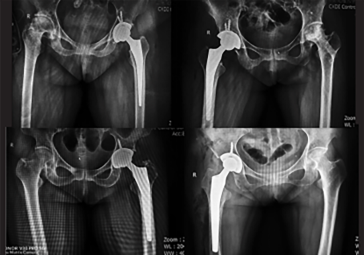

· 精準(zhǔn)執(zhí)行手術(shù)方案,消除徒手操作誤差。

· 髖關(guān)節(jié)置換:髖臼+股骨雙側(cè)規(guī)劃

· 制定詳細(xì)植入計(jì)劃,術(shù)前預(yù)演